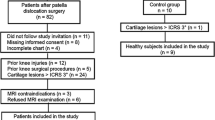

In a previous study [18], we demonstrated that quantitative sodium MRI with fluid suppression by inversion recovery with an adiabatic pulse at 7 T in cartilage could significantly differentiate asymptomatic subjects (controls) from patients with knee OA, as it is less sensitive to partial volume effects from surrounding synovial fluid than the acquisition without fluid suppression. In the present study, which is a follow-up to the previous one [18] and is based on the same patient cohort (12 of the knee OA patients agreed to come back), we measured and compared the variations of apparent sodium concentration (ASC) in the articular cartilage with sodium MRI with and without fluid suppression by adiabatic inversion, at baseline and 16-month follow-up in patients with knee OA. The aim of this pilot study is to evaluate the potential of sodium MRI to detect changes over time of ASC in articular cartilage in patients with knee OA. The long-term goal of this work would be to assess GAG depletion in knee OA patients with longitudinal measurements of cartilage ASC using sodium MRI.

Patients with OA

This study was approved by the institutional review board (IRB) and performed in compliance with the Health Insurance Portability and Accountability Act (HIPAA). All subjects provided written informed consent. We scanned the knee cartilage of 12 patients with OA, selected from the NYU Hospital of Joint Diseases knee OA cohort [19]. Subject characteristics are provided in Table 1. These patients fulfilled the clinical OA symptoms defined by the American College of Rheumatology [20] (ACR) as well as radiographic evidence of tibial-femoral knee OA with Kellgren–Lawrence (KL) grade of 1–4 on the standardized weight-bearing fixed-flexion posterior-anterior knee radiographs at baseline [21]. The exclusion criteria were any inflammatory arthritis, prior traumatic knee injury or surgery on either knee, or history of bilateral knee replacements.

Acquisition protocol

All subjects were scanned at baseline and follow-up with both R3D and IRW sequences. A summary flowchart of the protocol for data acquisition and analysis is presented in Supplemental Fig. S1. Data was acquired in the period November 2011–June 2012 for baseline and in the period February 2013–October 2013 for follow-up.